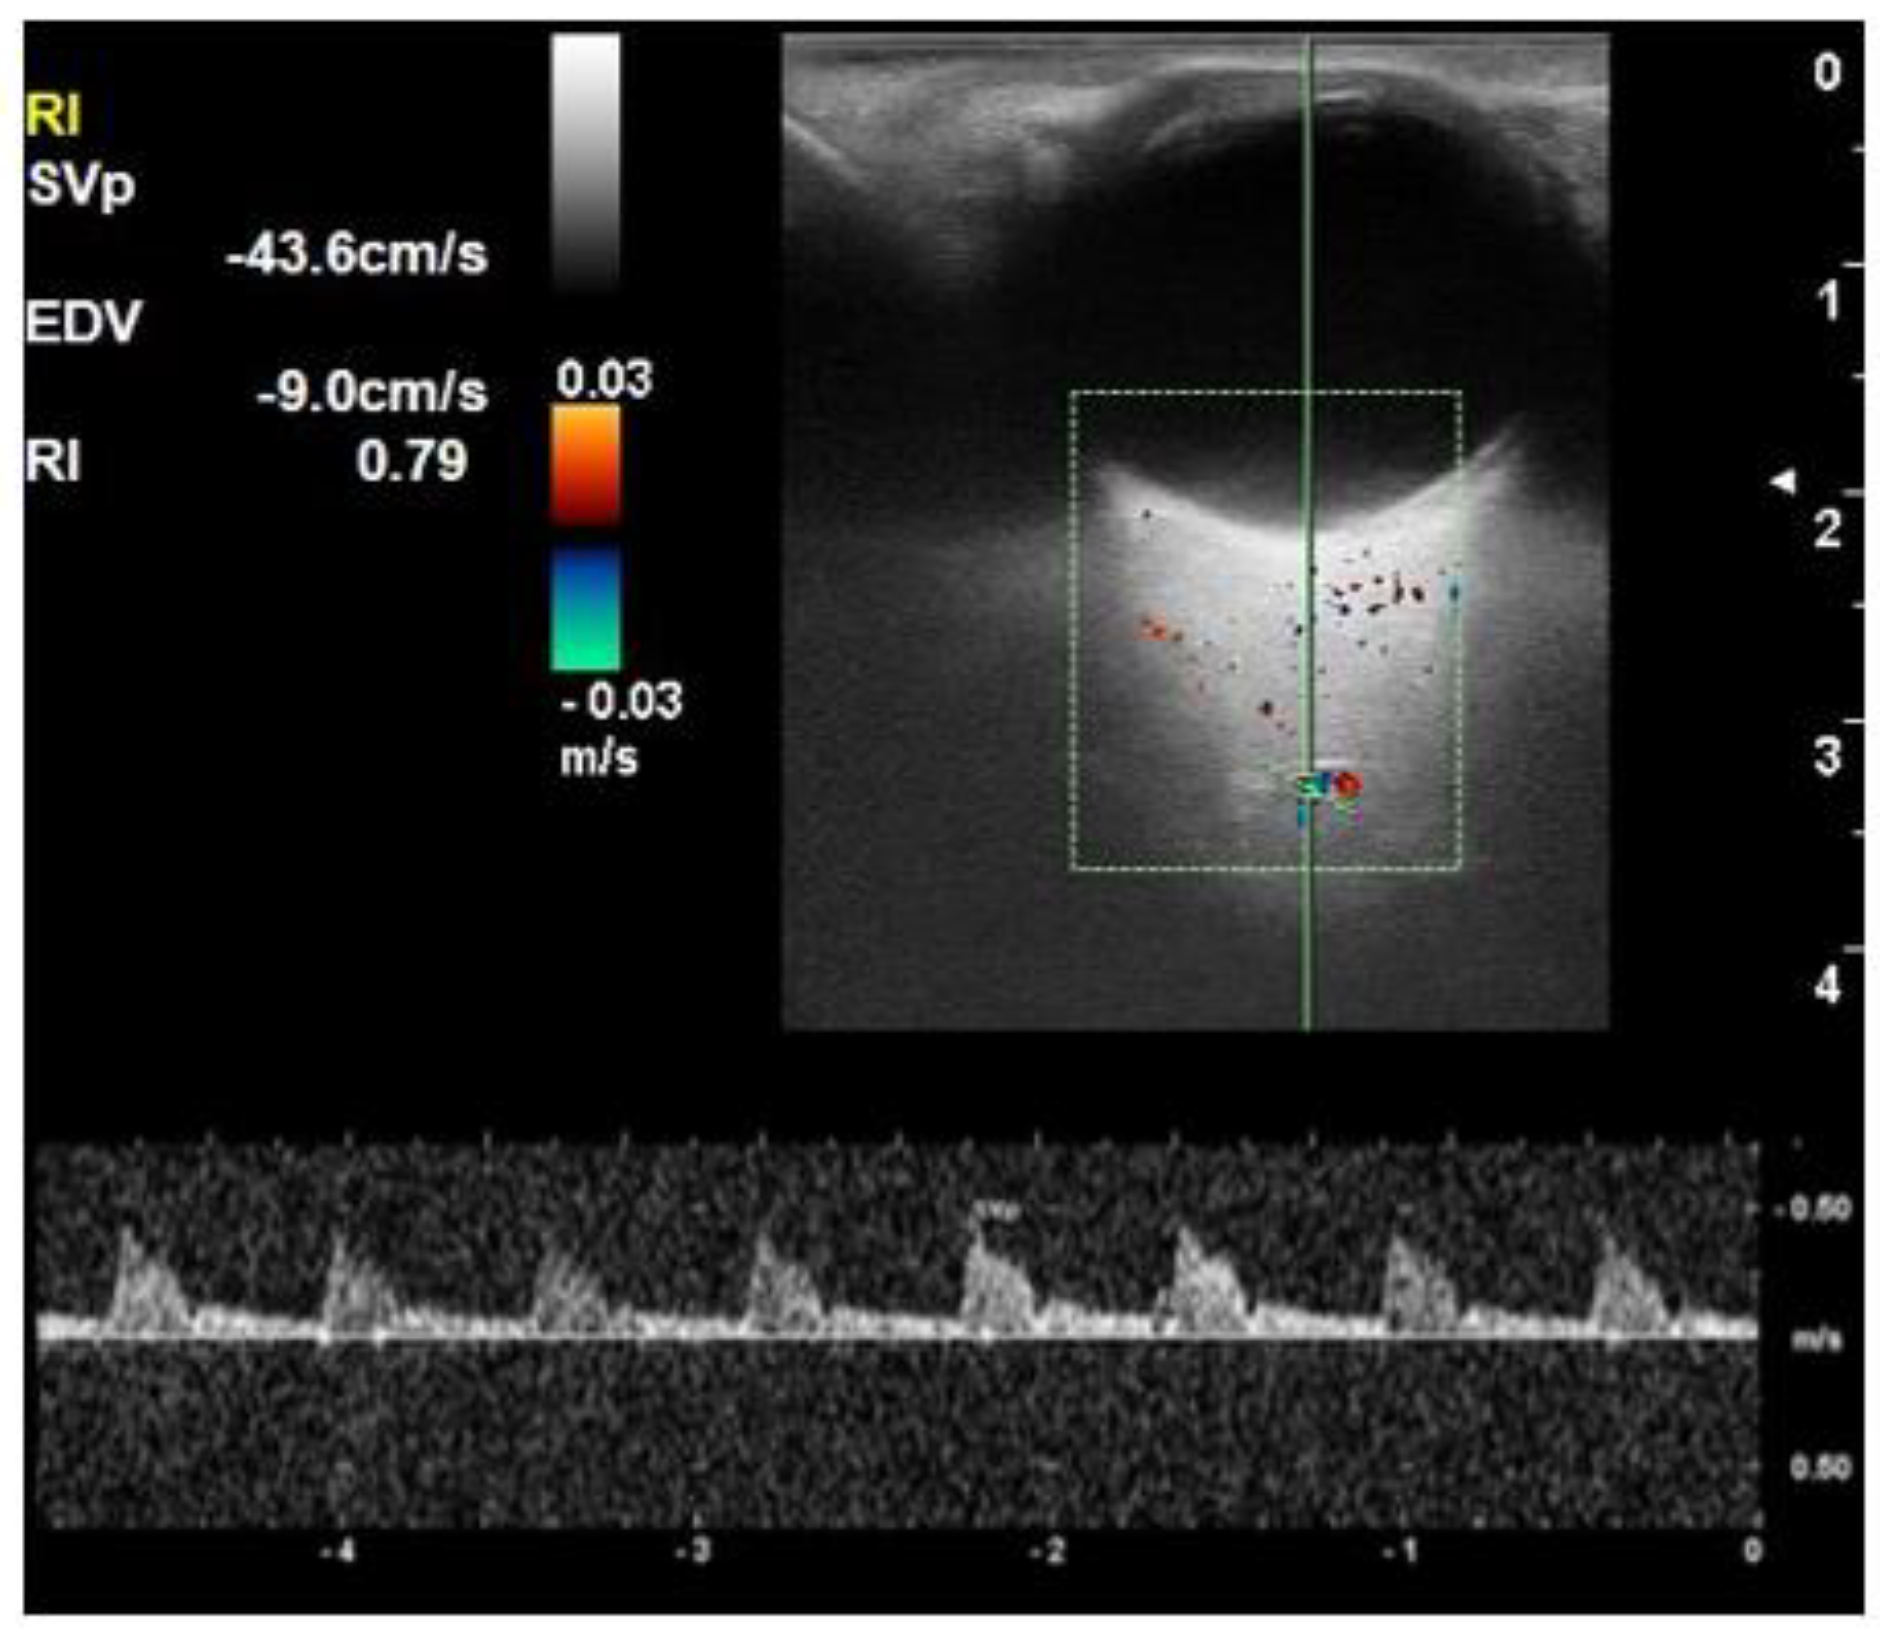

| PSV short posterior ciliary arteries (cm/s) | 19.1 ± 2.5 | 18.0 ± 4.2 | 16.7 ± 4.9 | 0.030 |

| EDV short posterior ciliary arteries (cm/s) | 5.9 ± 0.7 | 5.1 ± 1.3 | 4.3 ± 1.0 | <0.001 |

| RI short posterior ciliary arteries | 0.69 ± 0.03 | 0.71 ± 0.03 | 0.73 ± 0.5 | <0.001 |